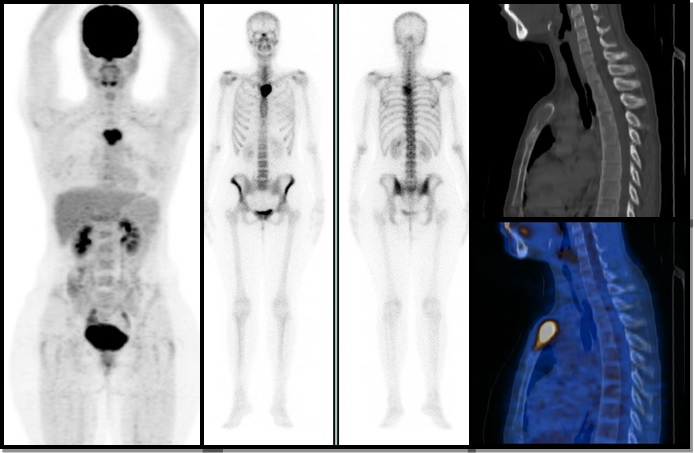

Figura 1.

Figura 1. Paciente de 55 años, con diagnóstico de cáncer de mama ductal infiltrante metastásico de 12 años de evolución. Las diferencias en la resolución y detección de lesiones óseas son notables al comparar la proyección de máxima intensidad del PET-CT (izquierda) con el rastreo óseo (derecha), siendo mucho mayor la sensibilidad para el primer método. De acuerdo a los hallazgos tomográficos, las lesiones óseas encontradas eran mixtas.